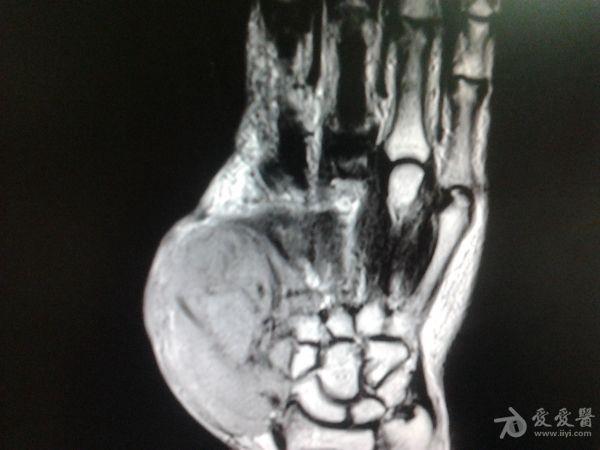

右第一掌骨、大多角骨肿瘤

男性患者,81岁,右手肿痛3个多月。无任何其它症状。体查:右手第一掌骨部肿胀明显,第一指活动受限,余四指活动可,腕关节活动小部分受限,活动时会痛。影像学检查如下。活检示:弥漫性大B细胞淋巴瘤。大家看看需不需要截肢?现在有人主张手术;有人主张不手术,直接化疗。大家有什么看法?

从以上资料看已经影响到腕关节了,还是截吧,不能姑息